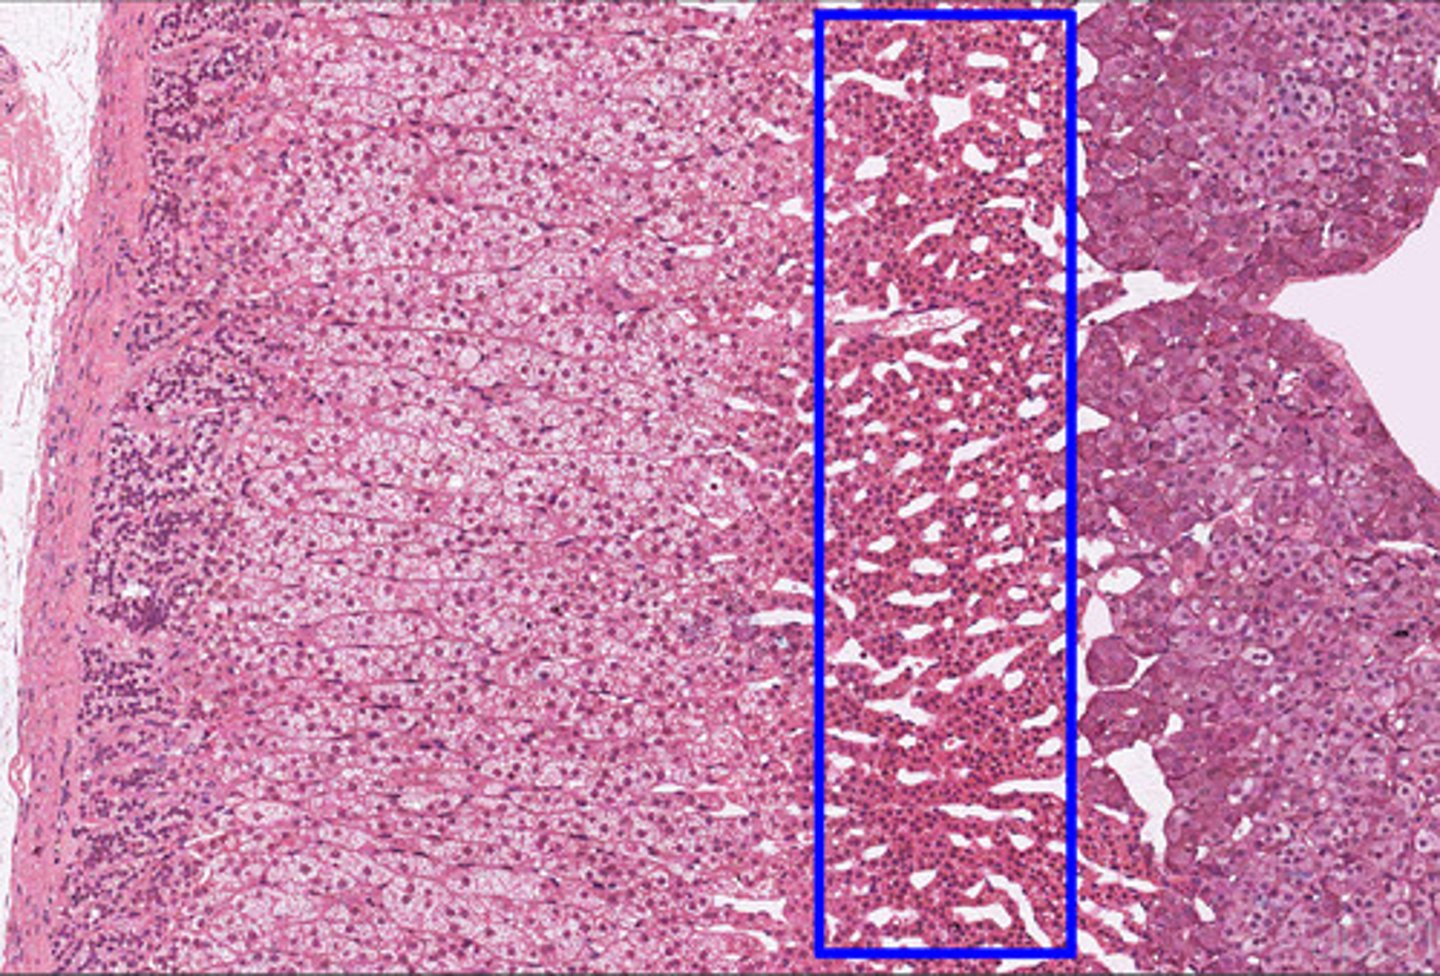

Adrenal gland

Adrenal cortex

Zona glomerulosa

Zona fasciculata

Zona reticularis

Adrenal medulla